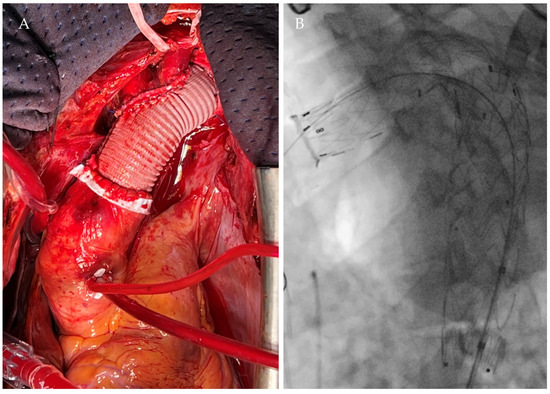

| Current Case-1 | 48 | M | Aortic arch | Cough | 25 years | Hybrid (ET + TEVAR) |

| Current Case-2 | 46 | M | Aortic arch | Asymptomatic | 21 years | Hybrid (carotid-subclavian bypass + TEVAR) |